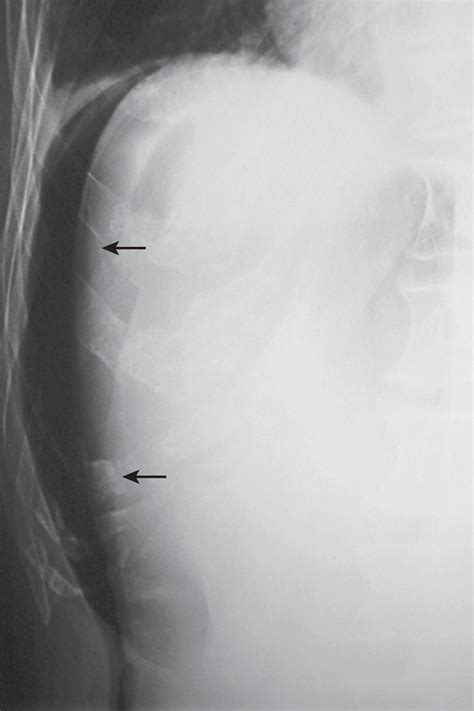

• Radiographic Imaging: It is frequently used in chest X-rays to detect small amounts of pleural effusion or pneumothorax that might not be visible in an upright or supine position.

When performing imaging in the Right Lateral Decubitus position, technicians must be precise with beam angulation and patient orientation. If the goal is to detect a pleural effusion, the patient is placed so that the side being examined is the "down" side. This allows the fluid to gravitate to the dependent portion of the thoracic cavity, where it is more easily identified against the chest wall. Conversely, if searching for free intraperitoneal air (pneumoperitoneum), the patient is often placed so that the potential air space is at the highest point.

Proper documentation is equally important. Radiographic films or digital images must be clearly marked as "Right Lateral Decubitus" to ensure that the interpreting radiologist understands the orientation of the anatomy. Failure to label correctly can lead to diagnostic errors, especially when distinguishing between various types of opacities or lucencies on a scan.